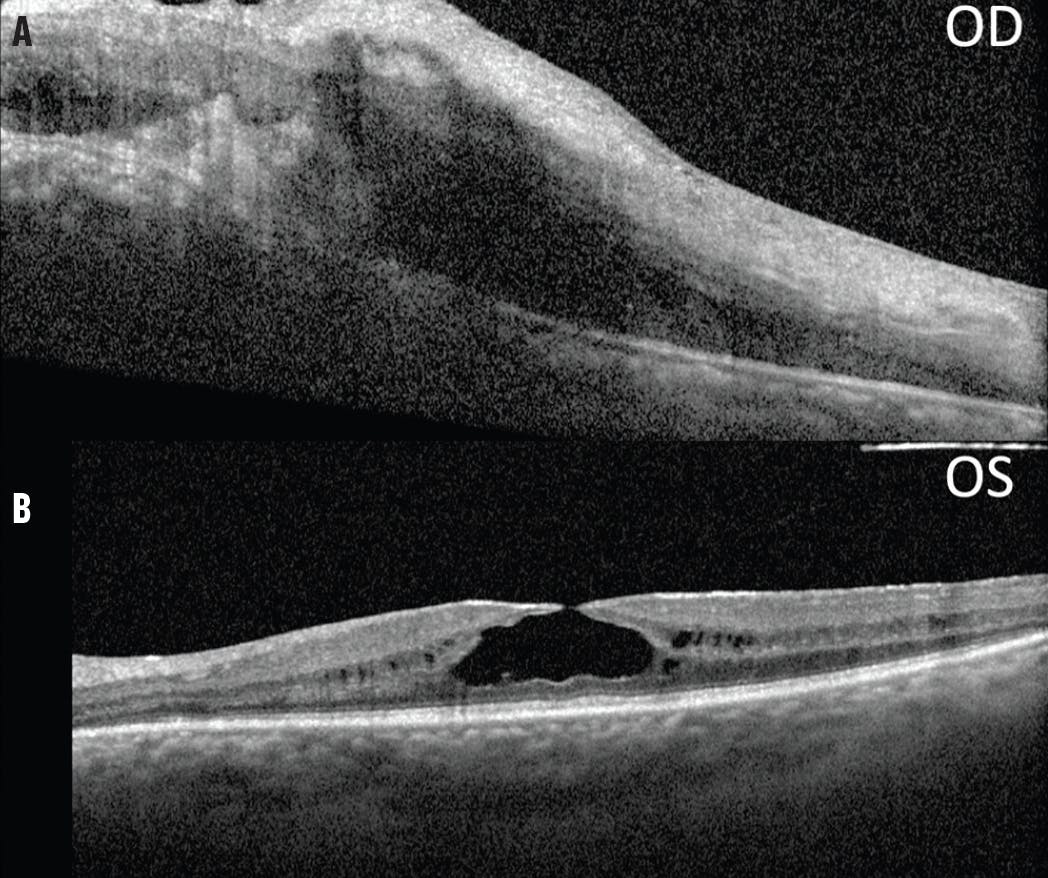

His VA was 20/50 OD and 20/40 OS. Visual field testing demonstrated moderate constriction bilaterally with a cecocentral scotoma in the right eye. Fundus autofluorescence (FAF) showed changes to the fovea and posterior pole in each eye (Figure 1A and B). OCT revealed further retinal changes (Figure 1C and D). Electroretinography demonstrated rod-cone dysfunction, with rods at 25% function bilaterally and asymmetric cone function (60% in the left eye and borderline in the right).

<p>Figure 1. FAF of the right (A) and left (B) eye showed a double hyperfluorescent ring around the fovea and posterior pole bilaterally. OCT of the right (C) and left (D) eye showed a thin retina, severe outer retinal atrophy, bare ellipsoid and outer nuclear layer at the fovea, and schisis-like CME bilaterally.</p>

Figure 1. FAF of the right (A) and left (B) eye showed a double hyperfluorescent ring around the fovea and posterior pole bilaterally. OCT of the right (C) and left (D) eye showed a thin retina, severe outer retinal atrophy, bare ellipsoid and outer nuclear layer at the fovea, and schisis-like CME bilaterally.